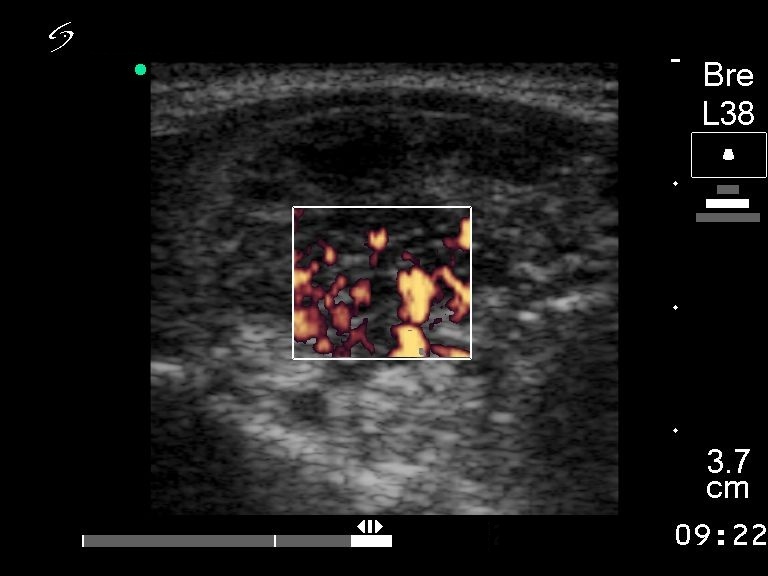

Ultrasonography revealed a solitary hypoechogenic nodule with increased intranodular flow.